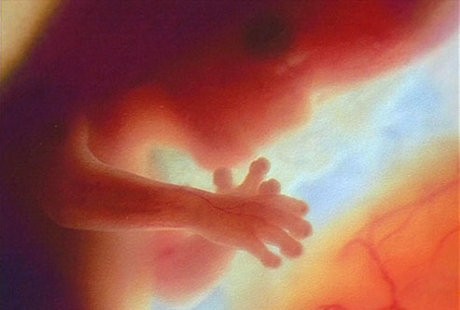

11. Minggu ke-12: Jari-jari Berkembang

Foto: webmd